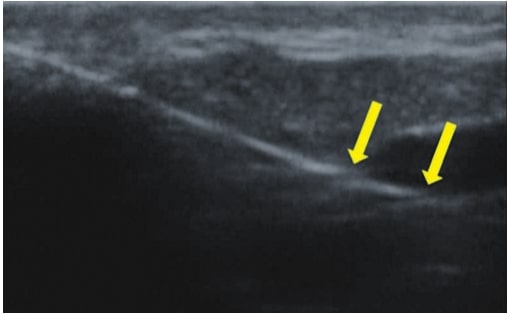

La escleroterapia es una técnica de cierre de vasos como resultado de inyectarles un esclerosante químico. En la actualidad, se aplica habitualmente y se caracteriza, sobre todo, por sus bajos costes y por el hecho de que es relativamente fácil de realizar. La escleroterapia está indicada principalmente para el cierre de venas reticulares mayores de 3 mm, pero también puede aplicarse si los vasos son más pequeños(10). En el caso de vasos menores de 3 mm, es más difícil introducir una aguja en su luz, lo que aumenta el riesgo de complicaciones(7). En tal situación, el HFU resulta de gran ayuda. Permite visualizar con precisión el curso del vaso y, posteriormente, facilita la realización del procedimiento con guía ecográfica (fig. 6). Así, gracias a la ultrasonografía, se ha eliminado el riesgo de administrar el esclerosante fuera de la luz del vaso, lo que conlleva necrosis. La imagen por ultrasonidos de alta frecuencia también puede utilizarse para monitorizar la eficacia del procedimiento.

El procedimiento microendovascular es una técnica endovenosa que se utilizó principalmente para el tratamiento de la insuficiencia de grandes venas del sistema superficial y que se ha adaptado para venas más pequeñas. Actualmente se utiliza en el cierre de venas reticulares y telangiectasias. El procedimiento consiste en insertar una fibra óptica láser estéril e inducir la coagulación de los vasos como resultado de la energía láser(7,11). Requiere la guía por ultrasonidos de alta frecuencia. Gracias a la imagen ecográfica, es posible evaluar el curso y la anatomía del vaso, la inserción precisa de la fibra óptica en los vasos (fig. 7), la coagulación del vaso y la eficacia del procedimiento.